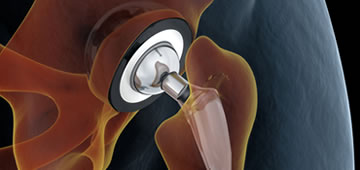

La artroplastia de cadera es el procedimiento quirúrgico mediante el cual se reemplaza la articulación de la cadera por un elemento artificial, conocido más comúnmente como prótesis, que suele estar compuesto de titanio u otras aleaciones metálicas. Existen muchos tipos de artroplastias de cadera, si bien la artroplastia total cementada suele ser la mejor opción a la hora de realizar esta intervención quirúrgica.1 La elección a la hora de colocar un tipo de prótesis u otra responde al tipo de lesión que ha propiciado la cirugía, así como la edad y características del paciente y los propios criterios del cirujano.